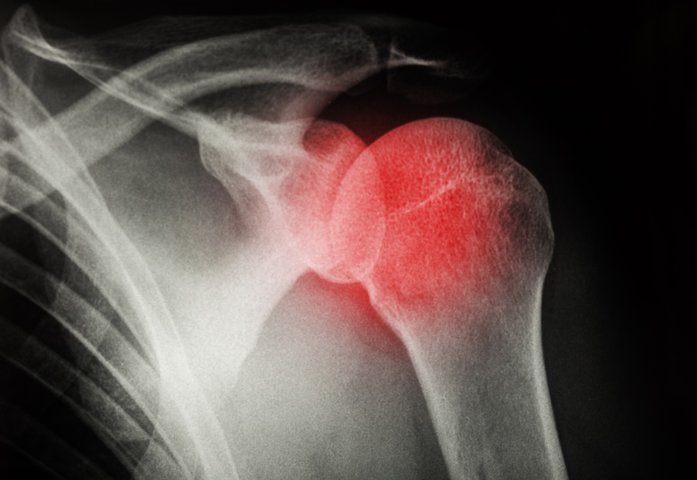

Shoulder surgery can be a life-changing procedure, but it’s important to understand the potential risks and complications that come along with it. With the right knowledge and preparation, you can reduce these risks and ensure a successful recovery. Stay tuned for our upcoming article, where we’ll provide you with all the information you need to navigate the world of shoulder surgery with confidence. Shoulder surgery is a common medical procedure that is performed to treat various conditions affecting the shoulder joint. While the surgery can provide great relief and improve the overall quality of life for many individuals, it is important to be aware of the potential risks and complications that may arise. Understanding these risks can help you make an informed decision and take necessary precautions before undergoing shoulder surgery.

In addition to the potential risks mentioned above, shoulder surgery can also be associated with certain complications that can affect the function and mobility of the shoulder joint. These complications include poor range of motion, shoulder stiffness, instability, and frozen shoulder.